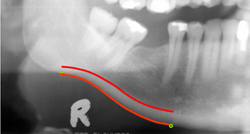

Postępujący spadek gęstości mineralnej kości, czyli osteoporoza, jest procesem skrytym, często ujawniającym się jedynie w postaci złamań kości biodrowej, kości nadgarstka lub kręgosłupa. W takim przypadku pacjenci wymagają długotrwałej rehabilitacji, co może wiązać się z długą niezdolnością do pracy czy poważnym spadkiem jakości życia pacjentów. Wczesne rozpoznanie początku osteoporozy umożliwiłoby pacjentom uzyskanie interwencji farmakologicznej lub dokonanie odpowiednich zmian trybu życia. Badacze z Uniwersytetu w Manchester uczestniczący w projekcie OSTEODENT stworzyli oprogramowanie umożliwiające analizę zdjęć pantomograficznych żuchwy. W Europie co roku wykonuje się miliony tego typu zdjęć pantomograficznych. W projekcie uczestniczyło 650 kobiet w wieku okołomenopauzalnym. Sprawdzono, u których pacjentek występuje osteoporoza, u których — normalna gęstość mineralna kości biodrowych oraz kości kręgosłupa, a u których — zmniejszona. Gęstość kości mierzono metodą podwójnej absorpcjometrii rentgenowskiej (ang. DXA, dual energy X-ray absorptiometry). Wykazano, że wyniki rutynowej manualnej oceny szerokości warstwy korowej kości na podstawie zdjęć rentgenowskich różnią się zarówno między stomatologami, jak i dla tego samego stomatologa, a przy tym procedura taka jest dość czasochłonna. Celem projektu było stworzenie automatycznego oprogramowania komputerowego do analizy zdjęć pantomograficznych w celu zmniejszenia do minimum błędu powtarzalności oraz uzyskania maksymalnej dokładności diagnostycznej osteoporozy. Do uczenia aktywnego modelu kształtu warstwy korowej kości zostały zastosowane zdjęcia pantomograficzne z innego dużego zbioru danych. Następnie program dokonywał automatycznego pomiaru szerokości warstwy korowej kości na podstawie dwóch punktów umiejscowionych na żuchwie. Stwierdzono znaczącą korelację między szerokością warstwy korowej kości oraz gęstością mineralną kości. Ponadto zastosowanie analizy ROC (ang. receiver operating characteristic) pozwoliło na uzyskanie klinicznie przydatnych wyników charakteryzujących się dobrą czułością i specyficznością. Zaletą stosowania oprogramowania jest niska interakcja z użytkownikiem lub jej brak, a także wysoka skuteczność diagnostyczna badania. Oprogramowanie ma dwojakie zastosowanie. Najbardziej oczywiste jest jego wykorzystywanie we wczesnej i dokładnej diagnostyce osteoporozy dostępnej podczas rutynowej wizyty stomatologicznej. Ponadto ocena gęstości żuchwy może znaleźć komercyjne zastosowanie przy planowaniu użycia implantów stomatologicznych. Takie analityczne oprogramowanie radiograficzne może być przydatne przy określaniu, czy pacjent nadaje się do zabiegu z wykorzystaniem implantów. Opis rysunku: Automatyczny pomiar grubości warstwy korowej kości na zdjęciu pantomograficznym.